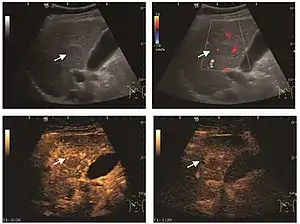

Focal nodular hyperplasia

It is a tumor developed secondary to a circulatory abnormality with abundant arterial vessels having a characteristic location in the center of the tumor, within a fibrotic scar. A radial vessels network develops from this level with peripheral orientation. The tumor's circulatory bed is rich in microcirculatory and portal venous elements. The incidence is higher in younger women and tumor development is accelerated by oral contraceptives intake. 2D ultrasound appearance is a fairly well-defined mass, with variable sizes, usually single, solid consistency with inhomogeneous structure. Rarely the central scar can be distinguished. Spectral Doppler examination detects central arterial vessels and CFM exploration reveals their radial position. CEUS examination shows central tumor filling of the circulatory bed during arterial phase and completely enhancement during portal venous phase. During this phase the center of the lesion becomes hypoechoic, enhancing the tumor scar. During the late phase the tumor remains isoechoic to the liver, which strengthens the diagnosis of benign lesion.